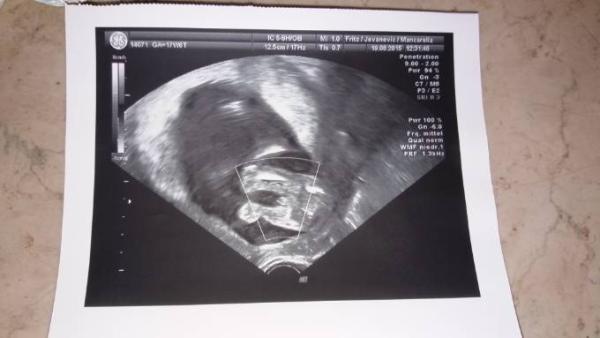

Ich zeig dir mal das Outing von meinem Sohn damals. Da kannst du ein bisschen vergleichen. War aber schon die 18.Woche.

Ich finde bei dir sieht es auch eher nach Junge aus. Aber abwarten, meine Tochter war auch erst ein Junge